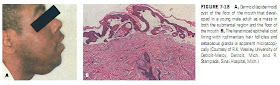

It is beyond the scope of this chapter to include detailed discussion of the clinical, radiographic, and histologic features of each of the different types of cysts that affect the jaws and adjacent oral tissues. The reader is referred to the more extensive coverage provided in most textbooks of oral pathology and oral radiology,FIGURE 7-18 A, Dermoid (epidermoid) cyst of the floor of the mouth that developed in a young male adult as a mass in both the submental region and the floor of the mouth. B, The keratinized epithelial cyst lining with rudimentary hair follicles and sebaceous glands is apparent microscopically. (Courtesy of R.K. Wesley, University of Detroit-Mercy, Detroit, Mich. and R. Stampada, Sinai Hospital, Mich.)